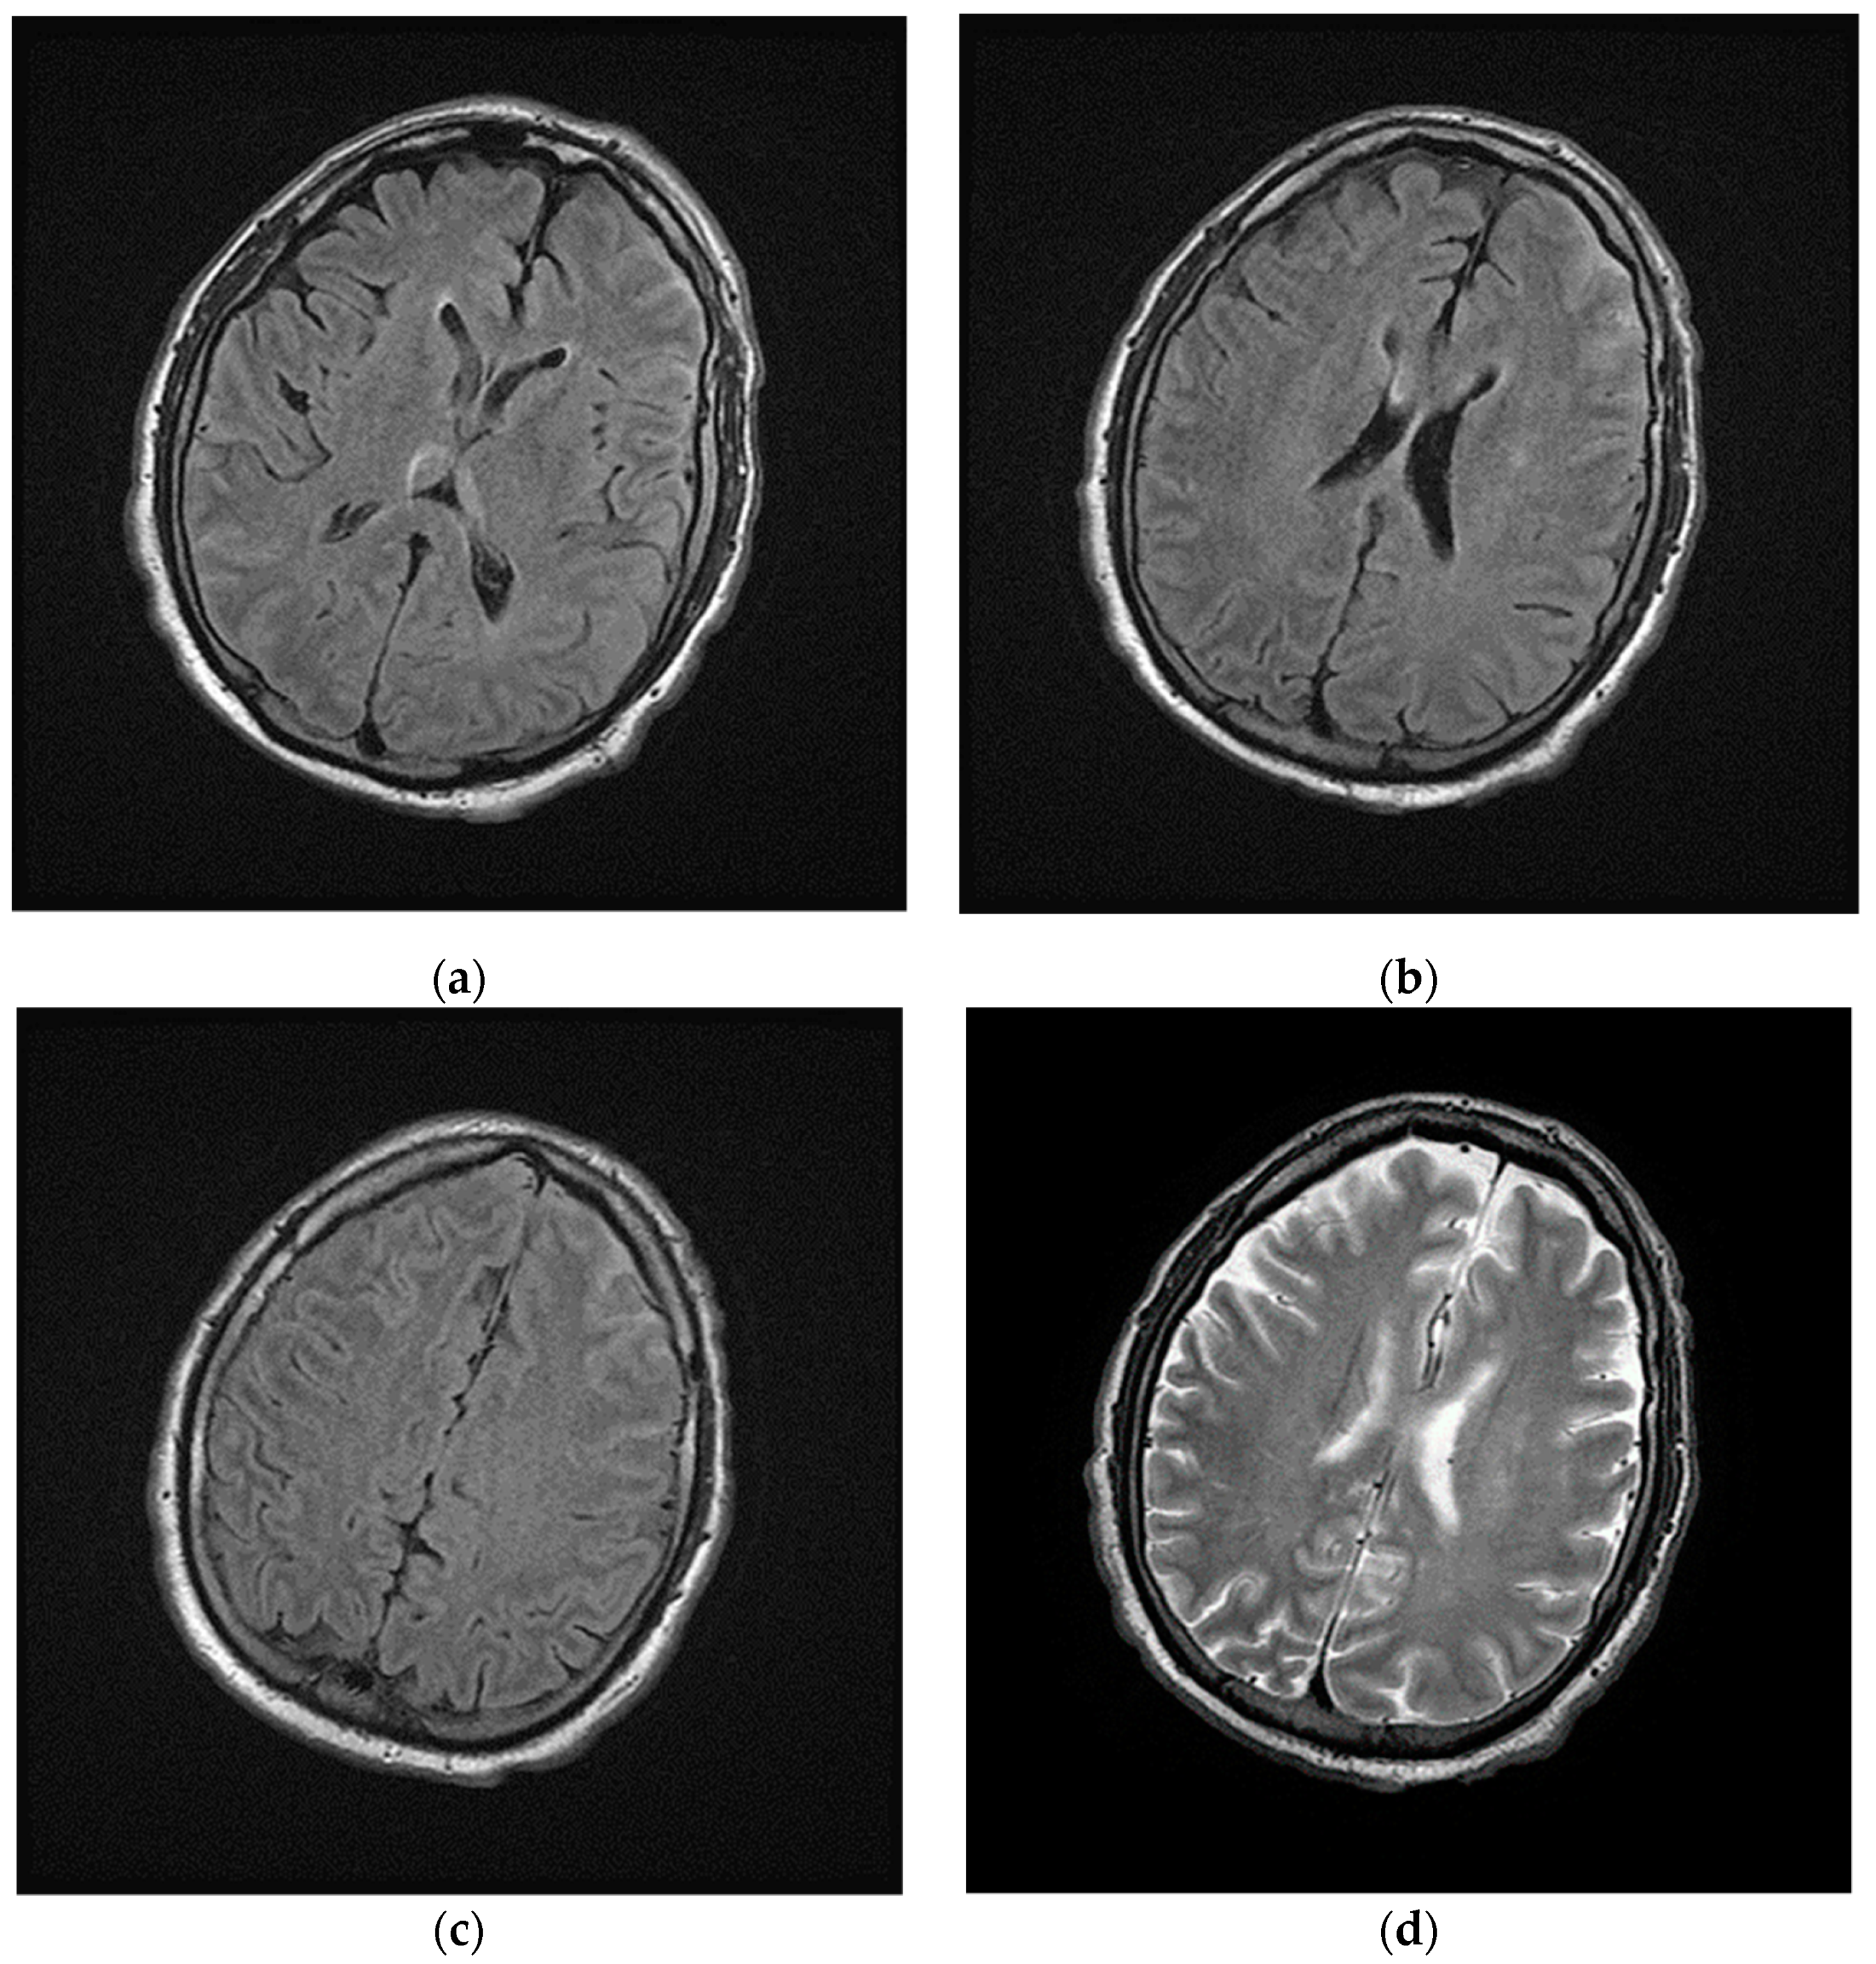

Laboratory results showed high levels of inflammatory markers (see Supplementary Material), the SARS-CoV-2 reverse transcription PCR test and the SARS-CoV-2 antibody test were positive (March 2020). The patient developed a worsening of respiratory status in the next 24 h after hospitalization, requiring respiratory support and intensive care; in this context brain-CT was not performed during the following days. Magnetic Resonance Imaging (MRI) of the brain was performed and showed hyperintensity signal of cerebral-spinal fluid, especially in the left frontal lobe, in the fluid-attenuated inversion recovery (FLAIR) images (Figure 2).

Figure 2.

Magnetic Resonance Imaging (MRI) of brain performed during intensive care. (a–c) Axial fluid-attenuated inversion recovery (FLAIR) images and (d) axial T2w image show cerebrospinal fluid hyperintensities in the left frontal lobe; in the same images no focal lesions of the cerebral parenchyma were detected.

In June 2020, three months after the positive results to COVID-19, the patient complained of chronic fatigue, headache, finger paresthesia, anxiety attacks and profound depression. The patient was subjected to brain MRI with intravenous paramagnetic contrast medium injection. In long TR images, numerous hyperintense focal areas were detected in the periventricular and subcortical white matter and in semioval centers. These imaging findings were referred to gliotic outcomes on a microvascular basis from a probable previous vasculitis episode. There were neither lesions of acute microischemic significance nor areas of pathological enhancement after paramagnetic contrast medium administration (Figure 4).

Figure 4.

Magnetic Resonance Imaging (MRI) of brain after discharged from the hospital. (a,b) Axial FLAIR and (c) axial T2w images show nonconfluent multifocal white matter hyperintense lesions; (d) On axial diffusion weighted image (DWI) the same lesions do not show impeded diffusion. These lesions were referred to gliotic outcomes.